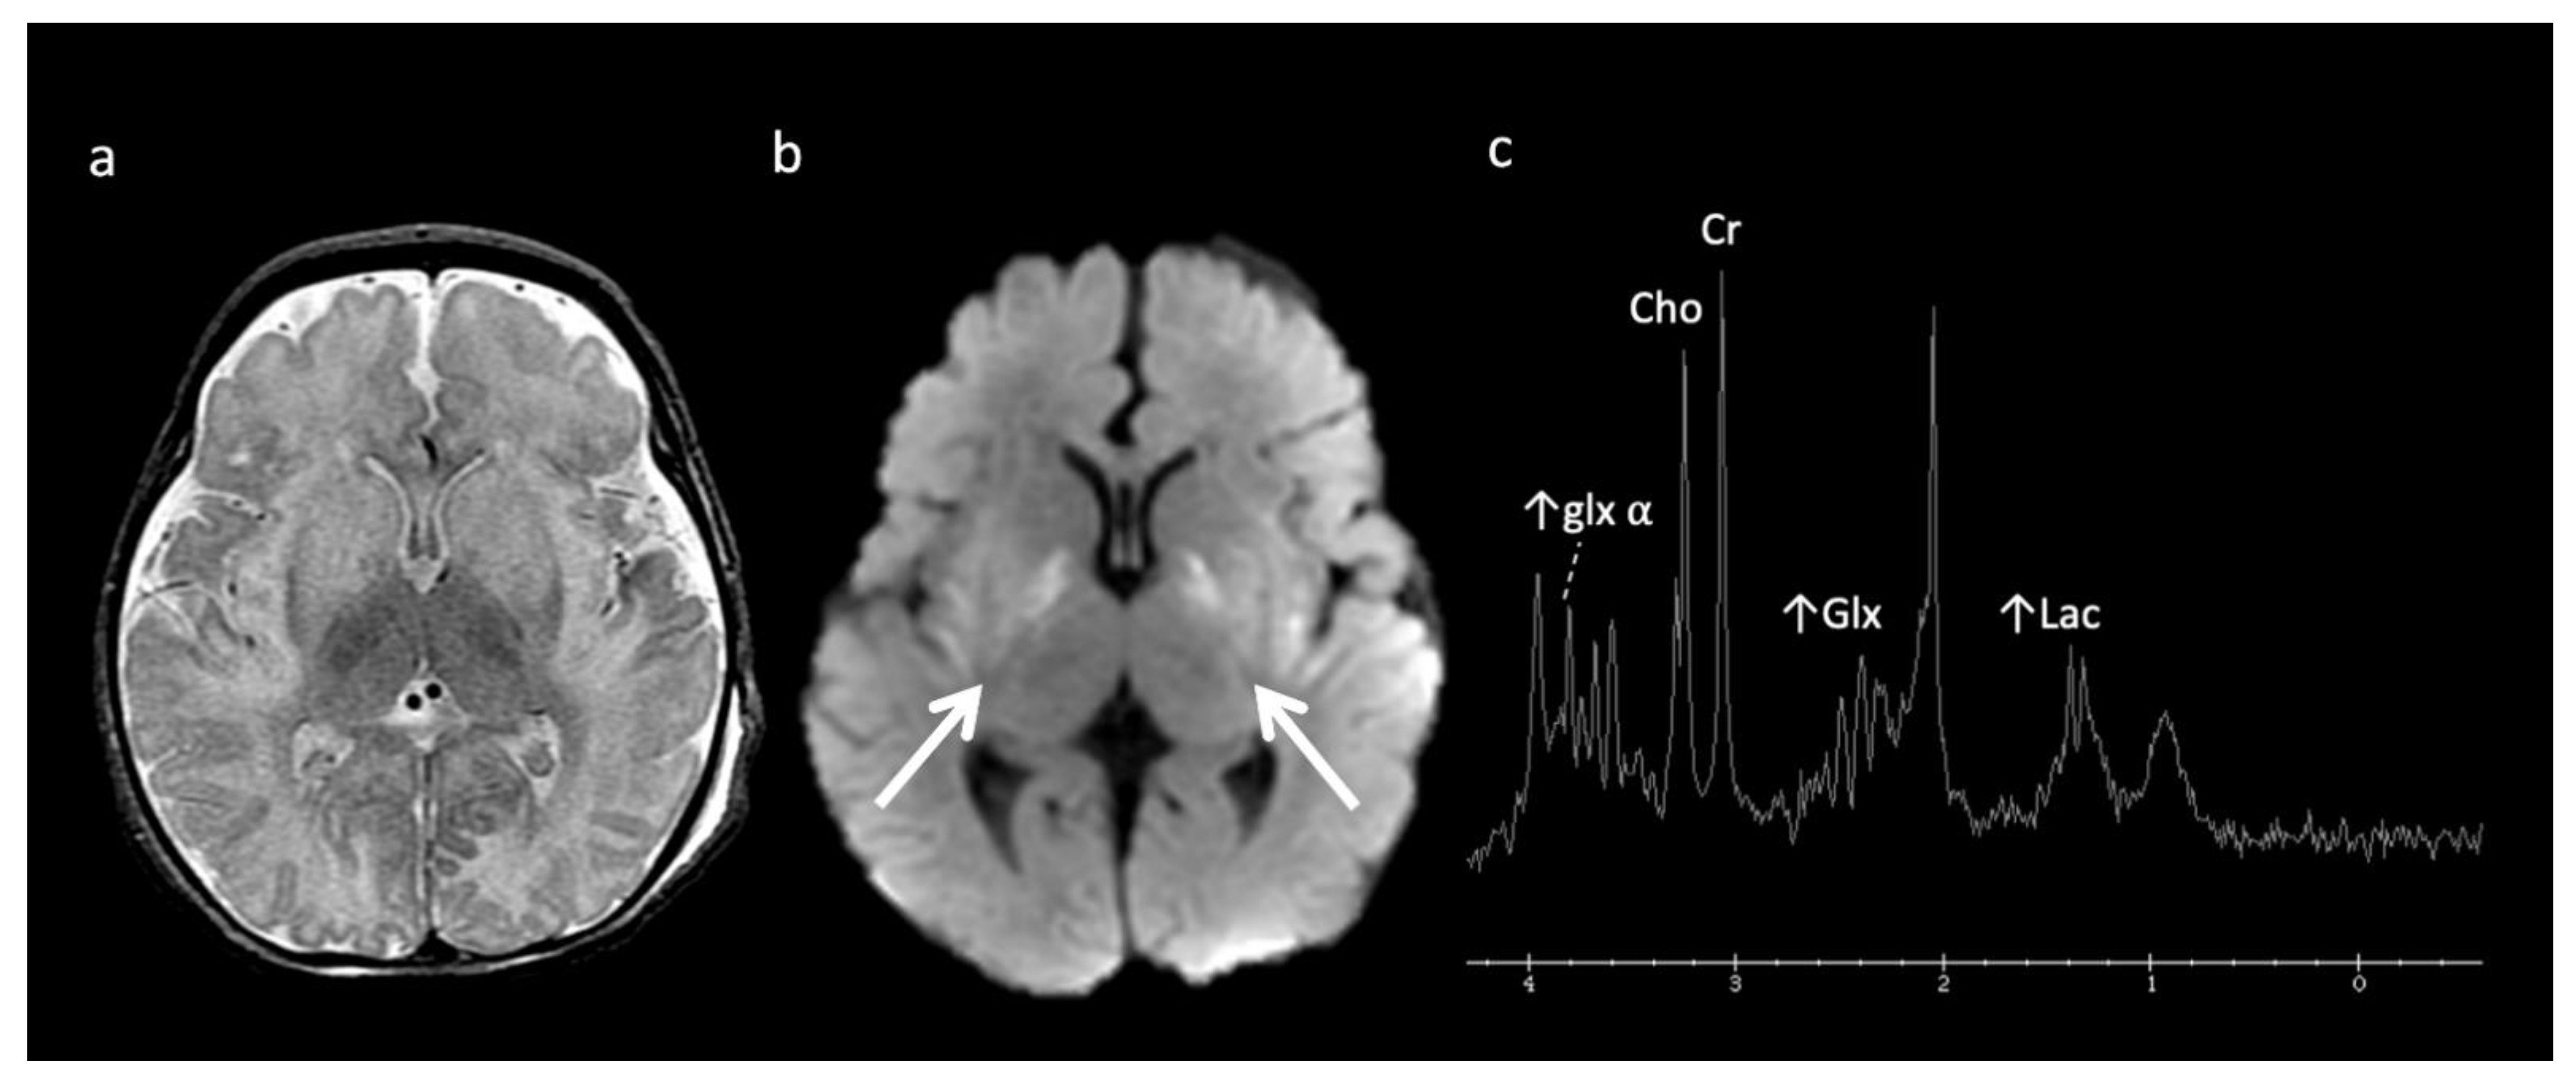

Urea Cycle disorders (Figure 2): Urea cycle disorders (UCD) are caused by defects in the conversion of ammonia to urea, resulting in accumulation of ammonia and glutamine (Gln). Gln is osmotically active, leading to diffuse edema in the cerebral cortex and subcortical white matter when in large concentrations. Brain MR findings characteristic to UCD-related hyperammonemia include a central pattern of edema involving the peri-rolandic, peri-insular, and basal ganglia regions, often sparing the thalami, which helps distinguish it from HIE [3,7,8].

Figure 2.

Example of hyperammonemia induced brain injury, as can be seen with urea cycle disorders. (a) Axial T2 and (b) axial diffusion weighted imaging (DWI) at the level of the basal ganglia show the typical pattern of hyperammonemic central brain involvement with perisylvian, periinsular, and basal ganglia signal hyperintensity consistent with mixed vasogenic and cytotoxic (white arrows, b) edema. (c) Single voxel (SV) short TE MRS demonstrates increased glutamine and glutamate (glx) with overlapping peaks at 2–2.5 ppm (2.4 ppm peak corresponds to elevated glutamine) and an elevated peak at 3.8 ppm consistent with glx associated alpha protons (glx-a). Lac and Cr are also elevated while Cho is depressed.

MRS shows elevated Glu/Gln peaks between 2 and 2.5 ppm during times of hyperammonemia, and a lactate doublet at 1.3 ppm when mitochondrial function fails to meet metabolic demand [3]. Glu/Gln resonances overlap at 1.5T but are more separable at 3T due to chemical shift dispersion; the peak centered at 2.4 corresponds more to glutamine [16]. There is also a commonly overlooked glx peak produced by alpha protons at 3.75 ppm. MI and Cho are usually reduced in chronic hyperammonemia, findings that can be highly suggestive of an underlying UCD in the correct clinical context [6,17].